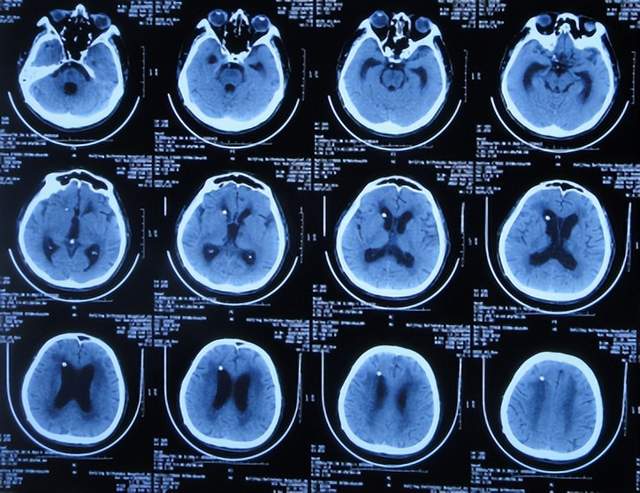

患者于2021年9月2日突发昏迷,急送至当地的山东省滨州市惠民县某医院,查头颅CT示脑出血破入脑室(图-1),急诊行双侧脑室外引流术;脑出血后血压偏低,给予输注入人血白蛋白。

图-1:2021年9月2日头颅CT

术后次日即2021年9月3日,患者意识转清醒,能简单言语,肢体可以遵嘱抬起;查头颅CT示双侧脑室引流术后,脑室积血(图-2)。

图-2:2021年9月3日头颅CT

双侧脑室外引流术后3天即2021年9月5日,查头颅CT示脑室内积血减少(图-3)。

图-3:2021年9月5日头颅CT

双侧脑室外引流术后6天即2021年9月8日,再次查头颅CT示仍有少量积血(图-4);给予常规拔除了双侧脑室外引流管,同时进行了腰大池引流术。

图-4:2021年9月8日头颅CT

腰大池引流术后4天即2021年9月12日,查头颅CT示脑室内积血基本消失(图-5)。

图-5:2021年9月12日头颅CT

拔除腰大池引流管后3天即2021年9月23日,查头颅CT示(图-6)后继续给予保守治疗。

图-6:2021年9月23日头颅CT

腰大池引流管拔除后13天即2021年10月3日,患者恢复至可以搀扶下行走约20米,能简单言语,查头颅CT较2021年9月23日认为没有明显变化(图-7)。

图-7:2021年10月3日头颅CT

但继续保留治疗20余天的时间内,患者逐渐出现意识变差,走路变差,至2021年11月3日(腰大池引流管拔除后31天),病情变重致不能走路,不能言语,查头颅CT(图-8)后考虑脑积水,给予腰椎穿刺治疗。

图-8:2021年11月3日头颅CT

但腰椎穿刺治疗7天病情无明显改善,于2021年11月10日(住院治疗2月余)出院回家休养,出院时头颅CT示仍有脑积水(图-9);出院时:意识差,不能走路,不能言语。

图-9:2021年11月10日头颅CT

出院1个半月后,因患者病情无改善,家属想做脑室腹腔分流术,于2021年12月22日前往上级的山东省滨州市某三甲医院就诊,查头颅CT示脑积水(图-10);但腰椎穿刺检查示颅内压低;胸部CT有肺部脓肿(片子丢失),暂时给予抗感染治疗。

图-10:2021年12月22日头颅CT

给予抗感染治疗个月后即2022年1月17日,肺部脓肿明显变小(片子丢失),查头颅CT仍脑积水(图-11),未给予脑室腹腔分流术,建议暂时回家休养,但患者意识仍不好,不能走路,不能说话,体型变消瘦。

图-11:2022年1月17日头颅CT